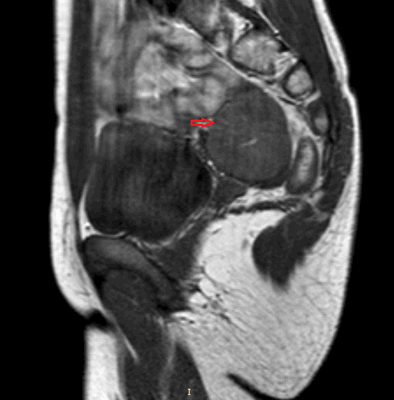

Яичники

Овариальные (расположенные в яичниках, яичниковые) опухоли наиболее часто проявляются болью в животе. При осмотре пальпируется опухоль в малом тазу, часто – в брюшной полости. Также за счет асцита (скопления в брюшной полости жидкости) увеличен живот. Нередко у девочек с таким диагнозом бывает лихорадка.

Самая часто диагностируемая герминогенная опухоль – это дисгерминома. Преимущественно ее обнаруживают во второй декаде жизни. У маленьких девочек встречается редко. Такое заболевания сравнительно быстро распространяется, поражая брюшину и второй яичник. Обычно новообразования односторонние, имеют большие размеры. В связи с этим частое явление – разрыв капсулы новообразования.

![Тератома яичника (УЗИ)]()

![Тератома яичника (МРТ)]()

Рисунок 3. – тератома яичника а –УЗИ, б — МРТ.

Злокачественные тератомы обычно проявляются неспецифической клинической картиной, которая связана с наличием опухоли:

- увеличенный объем живота;

- боль;

- нарушение менструального цикла (наблюдается не всегда).